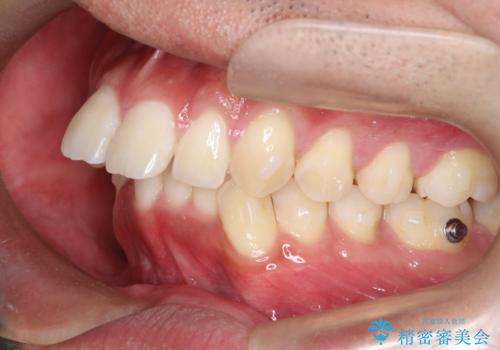

インビザラインによる出っ歯の矯正

- 出っ歯と下の歯のガタガタを主訴に来院されました。

上の奥歯を後方に移動させて、スペースを作り前歯を内側に引っ込める計画としました。

インビザラインによるマウスピース矯正で治療をすることとしました。

インビザラインをしっかり使用していただいたので、スムーズに治療をおえることができました。